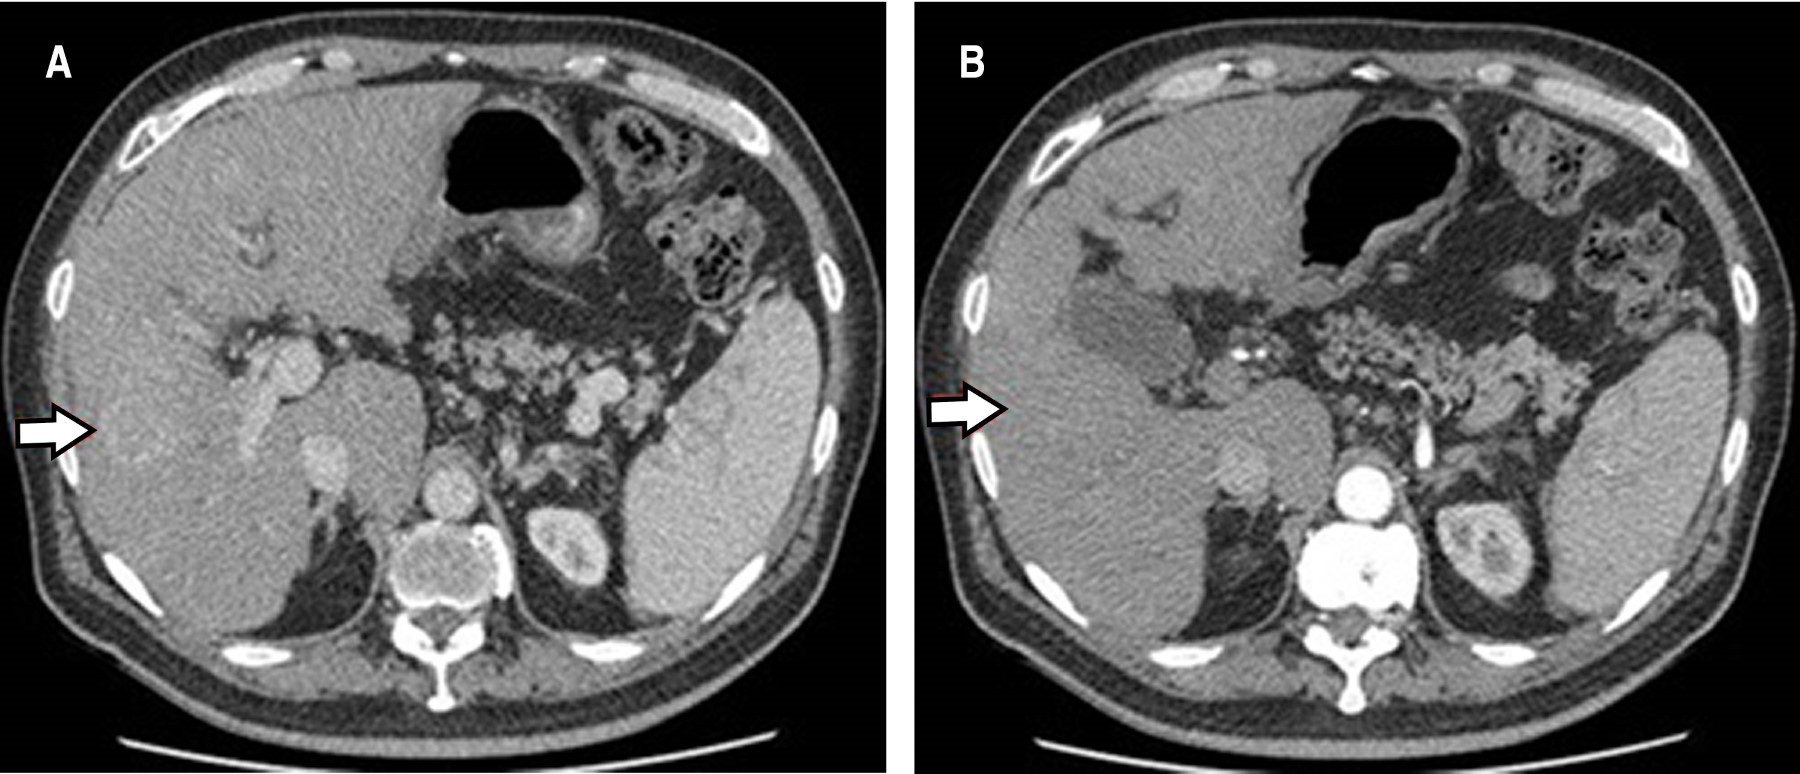

A la evaluación física paciente presenta pérdida de fuerza en dermatoma C6, con reflejos osteotendinosos 2/4, signo de Hoffmann negativo, prueba de Spurling positiva. Se realiza resonancia magnética cervical, evidenciando compresión medular en C3-C4, C4-C5, C5-C6. En resonancia magnética (RM) y tomografía axial computarizada (TAC) cervical se reportó lesión osteolítica del cuerpo vertebral C4, que involucra apófisis transversa izquierda, con componente de tejido blando que estrecha el foramen izquierdo (Figura 1A-B).

Se transfiere al paciente a la unidad de oncología, donde le realizan tomografía trifásica de hígado (Figura 3A y B). Se da tratamiento complementario con quimioterapia.